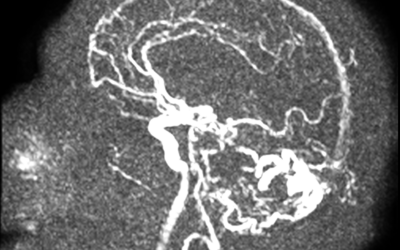

Caso de neurorradiología

Estudio de inestabilidad, se activó código ictus sin identificar oclusión de gran vaso.Enlace al caso de neurorradiología.